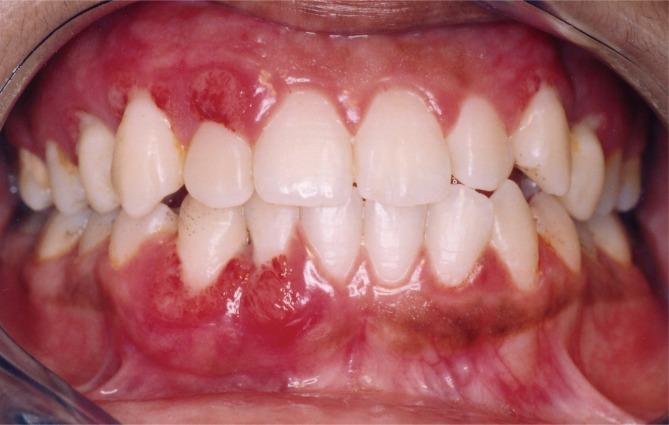

Aggressive periodontitis, especially in its severe form, was traditionally considered to have an unfavourable prognosis. It required a complex treatment and its stabilization was often achieved by surgical therapy. The aim of this study was to investigate the results of nonsurgical periodontal treatment in severe generalized forms of aggressive periodontitis.

Seven patients with 266 periodontal sites were examined. A significant difference was found between values, reported as medians with interquartile ranges, for PD at baseline (7.94 [7.33-8.19] mm) and both re-evaluation (4.33 [3.63-5.08] mm) and posttreatment (3.54 [3.33-4.11] mm) values (P=0.002). A significant difference was also found between values for CAL at baseline (9.02 [7.5-9.2] mm) and both re-evaluation (6.55 [6.30-6.87] mm) and posttreatment (6.45 [5.70-6.61] mm) (P=0.002). Inflammation was resolved and angular bone defects were repaired in all cases.

These therapeutic results suggest that this form of periodontitis could have positive outcomes after nonsurgical periodontal treatment. The reparative potential of tissue affected by severe aggressive periodontitis should encourage clinicians to save apparently hopeless teeth in cases of this form of periodontitis.